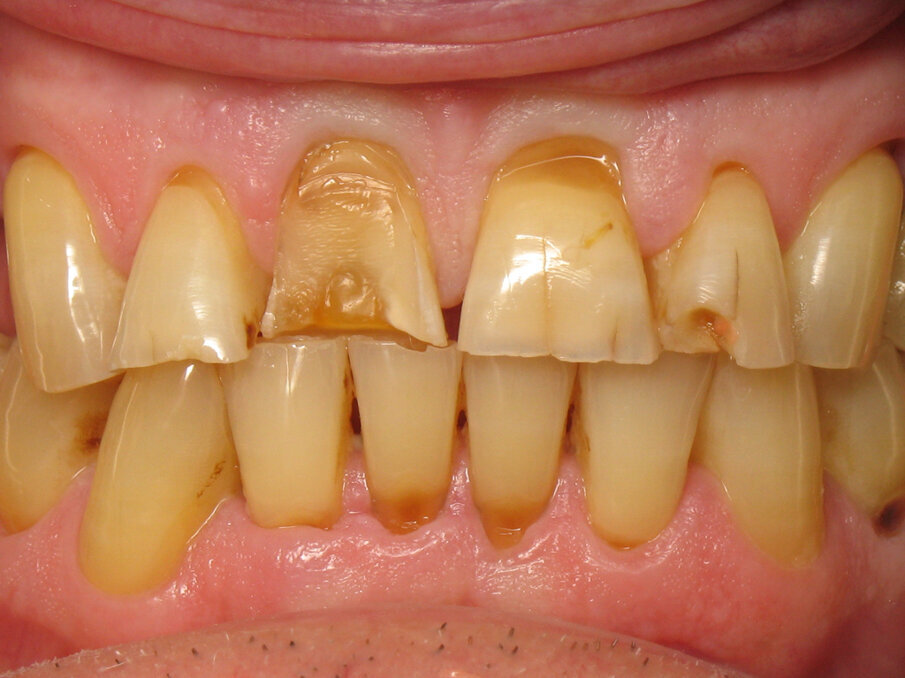

Fig. 11: Initial situation.

Fig. 12: Close-up of the initial situation.

Captured at the same time as Figure 10, Figures 11 and 12 show the initial situation of this patient, who came for a consultation to rehabilitate his maxillary incisors. The diagnosis revealed nocturnal bruxism as the origin of several areas of crown destruction: wear of the incisal edge, abfraction, missing restorations, cracks and a complex coronary fracture. It is easy to understand why the choice of material was zirconia. It is also easy to understand the motivations of this patient to recover his lost smile. This degradation over time is inevitable, but in this patient, it was particularly fast and aggressive. Reversing the course of time was therefore obvious in restoring the dental health of this patient.